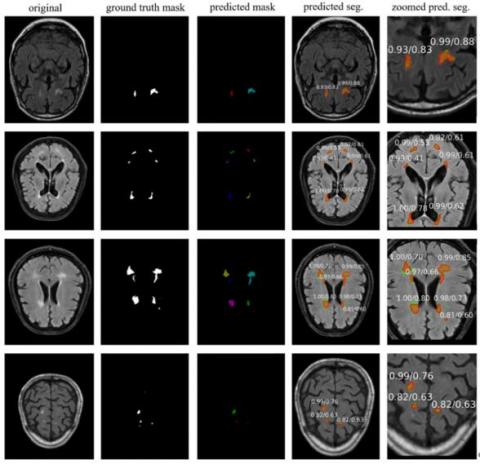

In experimental studies using the stroke dataset with the U-Net technique, 0.92 segmentation scores on pixel basis according to the DSC metric, and 0.89, 0.95 and 0.92 scores according to the PRC, RC and F1 metrics were achieved, respectively. The results from some of the ISLES 2015 MR images for stroke detection are shown in Figure 9. Here, the original MR image, ground truth masks of the stroke lesion area marked by the expert, and semantic segmentation masking of the lesion areas detected with U-Net are given for four different MR images. As a result of the experimental studies performed by the Mask R-CNN using the stroke dataset, 0.93 DSC score was achieved on pixel basis. In addition, as a result of the experiments, 0.97 PRC, 0.98, RC and 0.98 F1 scores were achieved.

The results of some images obtained in the experimental studies for the stroke dataset are shown in Figure 10. Here, the original MR image, masks of the ground truth marked by the expert, the segmented stroke area (predicted mask) as a result of the Mask R-CNN prediction, overlapping of segmentation and ground truth (predicted segmentation) and the zoomed image of the stroke lesion area are given for four different MR images. In Figure 10, masking in green represents the referenced ground truth, and the masking region in red denotes the region segmented by the proposed Mask R-CNN technique. The orange-colored region shows the overlap of the predicted segmentation and the ground truth masks.

Figure 10. Mask R-CNN segmentation results in ISLES 2015 dataset for some MR images